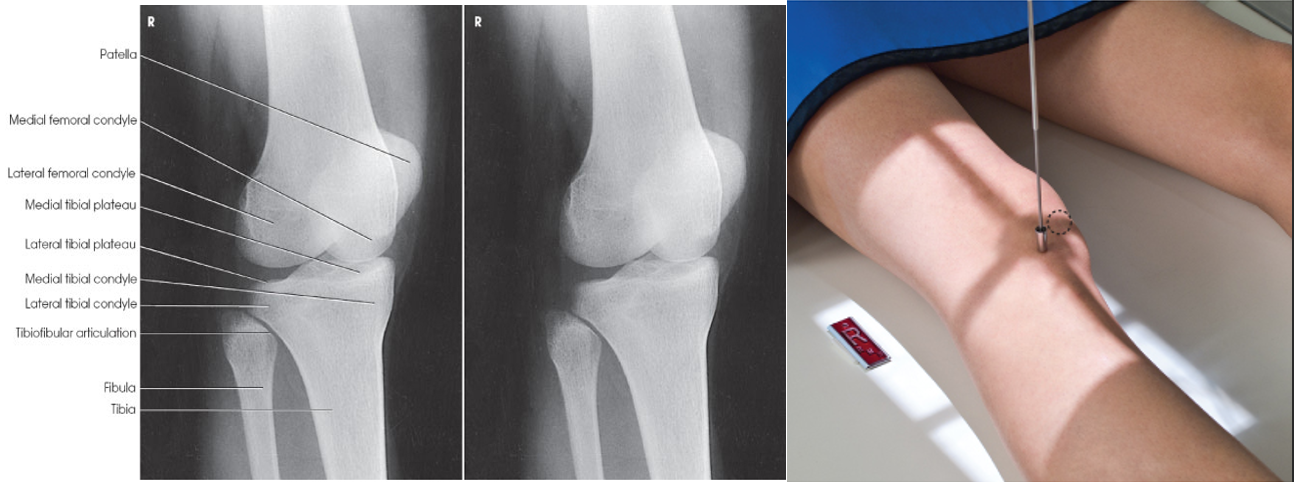

AP Knee

A

• IR 10x12 portrait, 40 SID

• Pt supine with no rotation of pelvis. Align & center leg and knee to CR, and table or IR. Rotate leg internally 3-5º for true AP. Average side patient CR will be perpendicular (19-24 cm measured at ASIS to table top)

**- ASIS to TT <19 cm 3-5º caudal

• ASIS to TT >25 cm3-5º cephalic***

• CR enters ½” distal to patellar apex (knee joint)